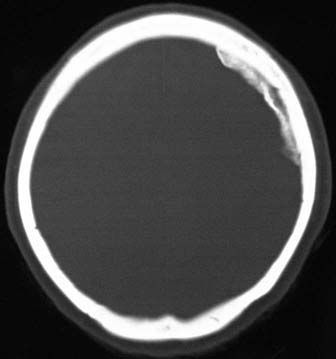

CaseFR01

- Age/Sex: 47F

- Chief Complaint: 後腹膜腫瘍の全身検索

- Clinical

Course: 約10ヶ月間心窩部痛を繰り返し,腹部CTで左後腹膜腫瘤が指摘された.手術で平滑筋肉腫の診断を得たが,骨シンチグラフィ異常を認めた.

- Lab. Data: BUN 8.1,Cr 0.61,Ca 8.1,Pi 2.8,CEA 正常,CA19-9

正常

- Images:

- Skull X-ray, XCT